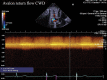

Introduction: Optimal positioning of double lumen bicaval canula for extracorporeal membrane oxygenation (ECMO) support used as a rescue measure in refractory hypoxaemia is essential to facilitate adequate oxygenation, prevent recirculation and avoid complications. Method: Echocardiography via transoesophageal or transthoracic windows can be used as guidance and as a surveillance technique to prevent cannula malposition. We describe a case of Double-Lumen Bicaval VV ECMO cannula malposition leading to a massive retrograde hepatic venous flow. Conclusion: Rapid echocardiographic diagnosis was pivotal in preventing potentially fatal complications.